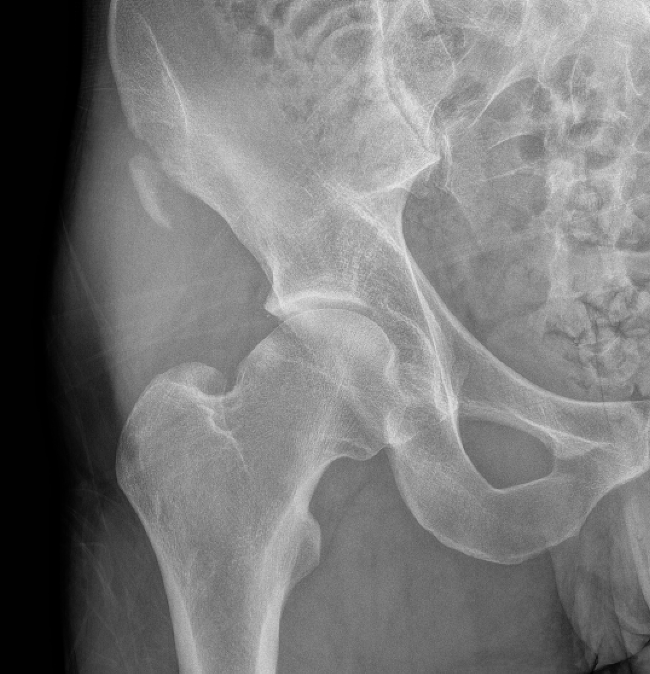

Xray

Ischial tuberosity avulsion 1Ischial tuberosity avulsion 2

Ischial tuberosity avulsion